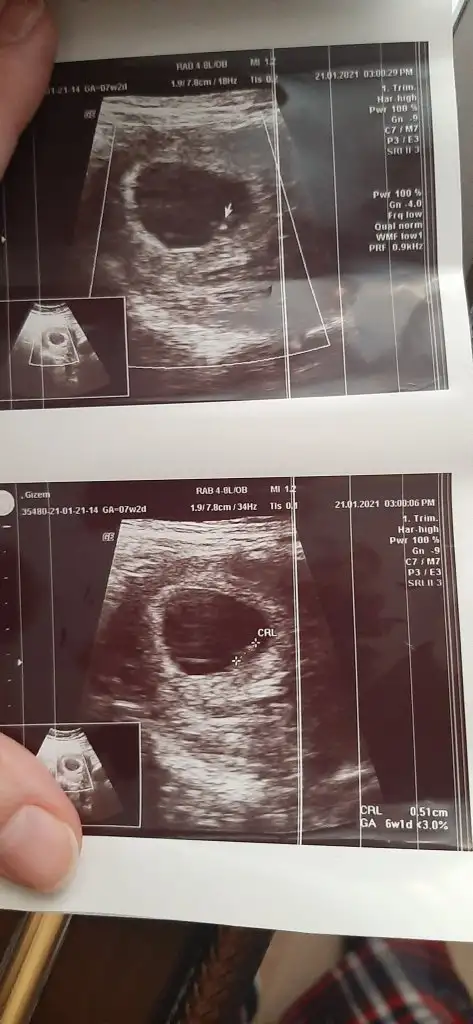

Kiz gibibana da bakar mısınız karından ultrason 6+1Eki Görüntüle 2773762

Erkek gibiEn baştaki 6+6 günlük olan diğer son 2 fotoğrafta 10 haftalık benimde tahmin edebilir misiniz